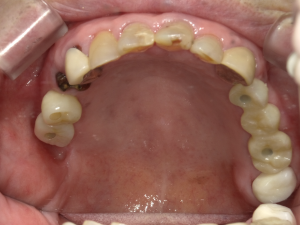

50代 インプラント治療(右上3左上3のみGBR)

| 年代・性別 | 50代・男性 |

|---|---|

| 主訴 | 入れ歯が合わず毎日ヨーグルトしか食べることができないので、しっかり咬めるインプラントにしたい。 |

| 部位 | 右下⑦⑥5④ 上顎③2①①2③ 左下67 |

| 治療期間 | 約9ヶ月 |

| 費用 | ¥4,273,500(税込) |

| 副作用・リスク |

|